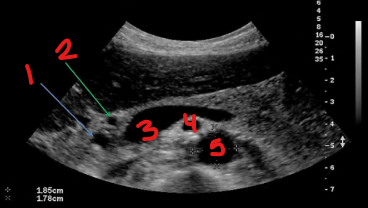

Identify this image.

CBD

GDA

Portal confluence

SMA

Aorta